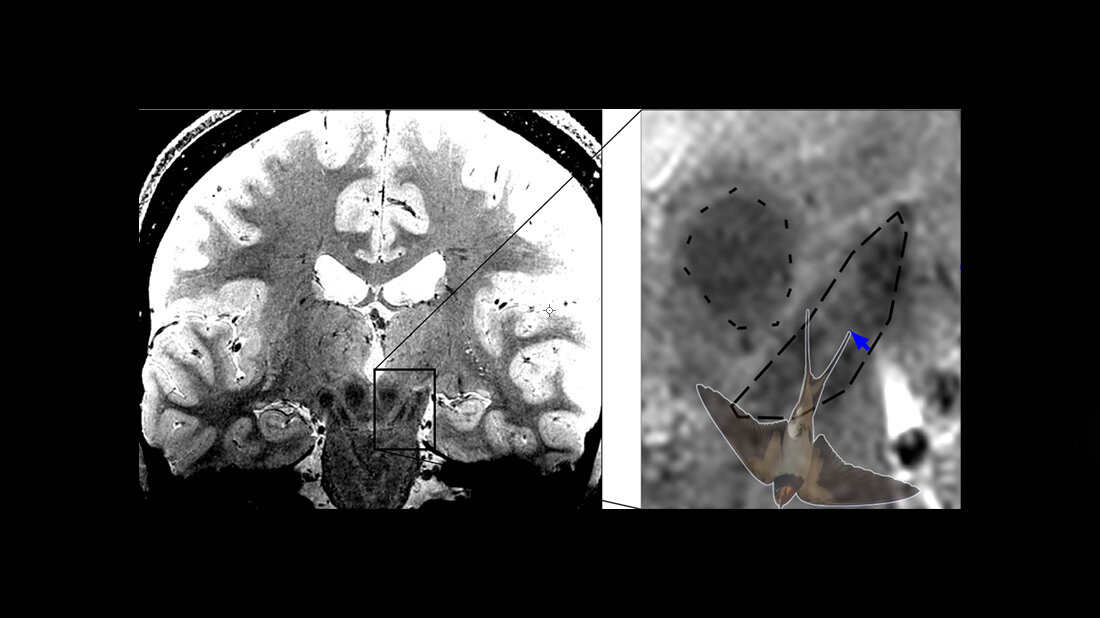

Bei Parkinson sterben dopaminproduzierende Nervenzellen in der Substantia Nigra im Mittelhirn ab, was bei den Betroffenen zu Bewegungsstörungen wie Verlangsamungen, steifen Muskeln und Zittern führt. Besonders stark und früh sind die Nervenzellen im Nigrosom 1 innerhalb der Substantia Nigra betroffen. Mit hochaufgelöster MRT-Bildgebung ist die Abbildung des Schwalbenschwanzzeichens möglich, welches sich im hinteren Drittel der Substantia nigra befindet und nach gängiger Lehrmeinung Nigrosom 1 entspricht. Bei gesunden Menschen erkennt man im MRT-Bild eine signalreiche längliche Struktur, die vorne und an den Seiten von signalarmen Arealen umgeben ist. Diese besondere Form erinnert an einen Schwalbenschwanz, daher spricht man auch vom Schwalbenschwanzzeichen (engl. Swallow tail sign). Nach der gängigen Interpretation des Zeichens führt das Absterben der Neuronen im Nigrosom 1 bei Parkinson-Betroffenen dazu, dass das Schwalbenschwanzzeichen schließlich nicht mehr erkennbar ist. Ist das der Fall, liegt mit hoher Wahrscheinlichkeit eine Parkinson-Erkrankung vor.

Malte Brammerloh und seine Kolleginnen und Kollegen haben nun mikroskopische 3-D-Untersuchungen von menschlichen Gehirnen nach dem Tod mit MRT-Technik kombiniert, um zu zeigen, dass Nigrosom 1 und das radiologische Schwalbenschwanz-Zeichen sich nur teilweise überlappen und in der Tat sehr unterschiedlich sind. Die Wissenschaftler/-innen plädieren daher dafür, das Schwalbenschwanz-Zeichen nicht mit der Region Nigrosom 1 gleichzusetzen. Dies erlaube eine Neuinterpretation des diagnostischen Schwalbenschwanz-Zeichens und eröffne gleichzeitig neue Wege zur spezifischen Nigrosombildgebung. Brammerloh ist sich sicher: „Wir glauben, dass man mit diesem neuen Wissen besser versteht, wie Anatomie und MRT-Kontraste zusammenhängen und wie neue MRT-Marker für die frühe Diagnose von Parkinson entwickelt werden können.“